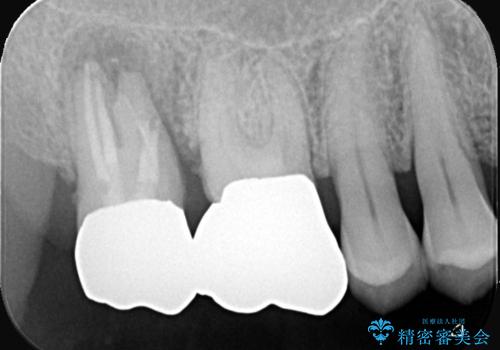

- 当院にて根管治療を行いましたが、病変の改善が得られなかったため、インプラント治療を行う方針といたしました。

抜歯即時埋入の適応と判断し、抜歯当日にインプラント埋入を行う「抜歯即時埋入」にて処置を実施しました。